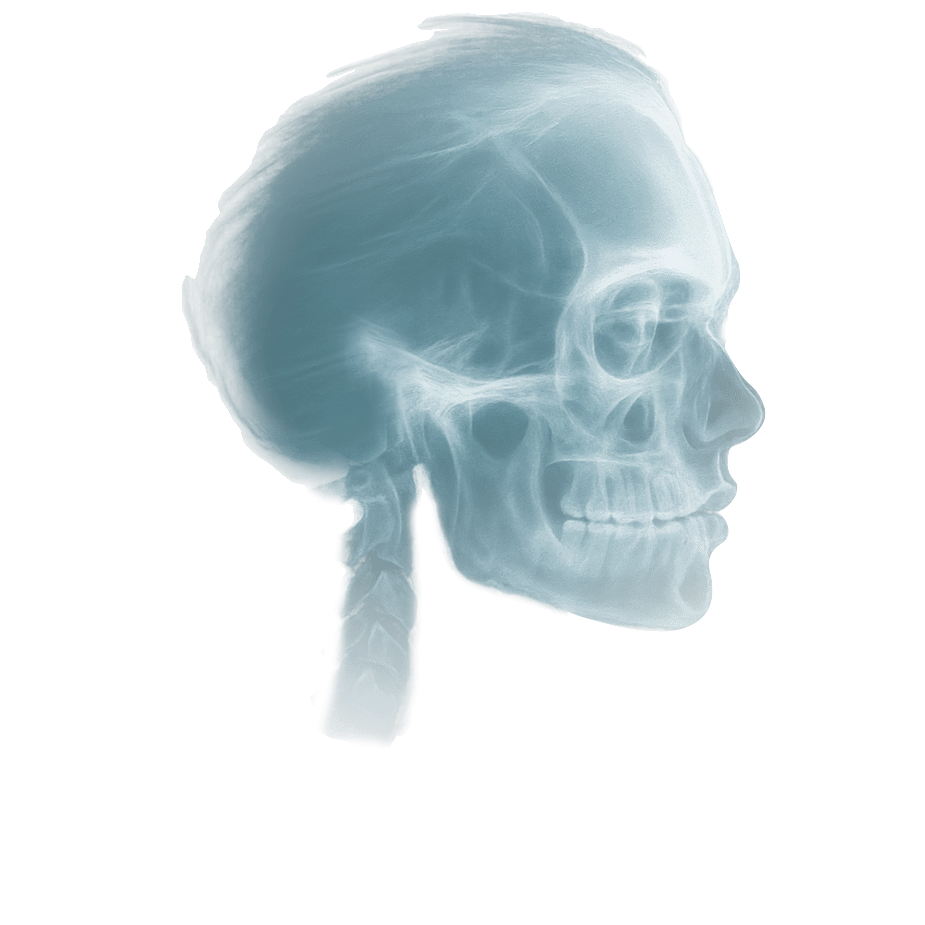

Screening Report is a concise, text-only summary designed for straightforward cases or when you simply need to rule out pathology. This option is often used when an image was taken for a specific purpose, but you’d like a radiologist to review the entire scan as part of our dental teleradiology services, confirming there are no incidental findings across the full set of medical images.

Advanced Report includes annotated images, detailed key findings, and practical clinical recommendations. Choose this option for treatment planning, complex cases, referrals, or when visuals are needed to communicate findings with colleagues or patients and support confident clinical decisions in the final report.